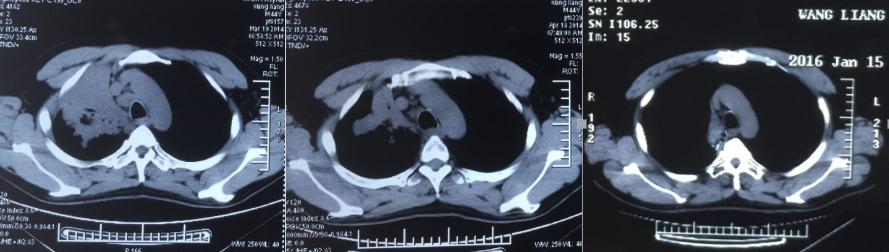

44岁的王先生在2014年被诊断为右上肺低分化腺癌,已无手术机会,在当地进行了卡铂+培美曲塞三周期化疗,期间服用易瑞沙,病情仍然进展。PET/CT示右侧中央型肺癌伴纵隔淋巴结转移。

在经过治疗后,王先生的病灶明显缩小,咳嗽症状减轻。由于A45治疗具有很好的远观效应,治疗后能够持续性的*伤杀**肿瘤细胞,因此王先生的病灶在治疗结束后两年完全消失!至今王先生的身体状况良好,无任何复发转移征象。

治疗前 治疗后 治疗后两